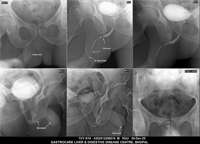

Section: URETHROGRAM

Total: 95 Cases

All Categories BaM Enteroclysis Loopogram BaE Fistulogram Urethrogram HSG